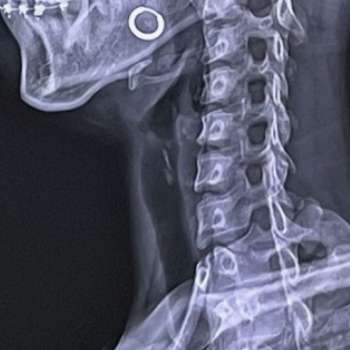

목디스크, 또는 경추 추간판 탈출증(Cervical Disc Herniation)은 목 부위의 디스크가 탈출하거나 돌출되어 신경을 압박하는 상태를 말합니다. 이로 인해 통증, 감각 이상, 근력 저하 등이 발생할 수 있습니다. 목디스크의 원인은 매우 다양하며, 이를 이해하기 위해서는 해부학적, 생리학적, 그리고 생활 습관적인 요인들을 모두 고려해야 합니다. 전문가적 입장에서 목디스크의 주요 원인 10가지를 매우 상세히 설명하겠습니다.

급성 외상은 목디스크를 일으킬 수 있습니다. 교통사고나 낙상, 스포츠 부상 등으로 인해 목에 강한 충격이 가해지면, 디스크가 갑자기 탈출할 수 있습니다. 외상으로 인한 디스크 손상은 즉각적인 통증과 함께 신경 압박 증상을 동반할 수 있습니다. 외상 후 목의 움직임 제한, 근육 경직, 신경학적 증상이 나타나면 즉각적인 의학적 평가와 치료가 필요합니다.